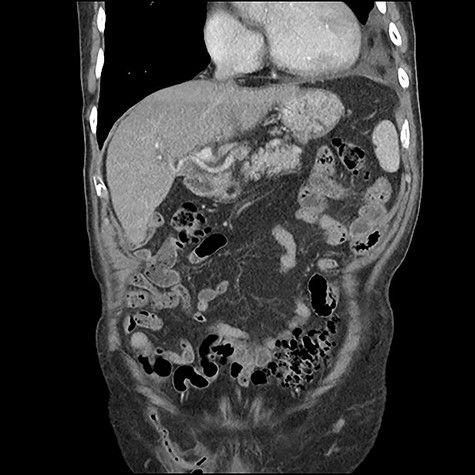

A 90 year old gentleman was admitted on the acute surgical take with right hypochondrium pain. On examination he was pyrexial, tachycardic markedly tender in the right upper quadrant of his abdomen. There was also a reducible non-tender right-sided inguinal hernia present. His past medical history included atrial fibrillation (anti-coagulated with apixaban) alongside ischaemic heart disease, osteoarthritis and a degree of congestive cardiac failure with poor exercise tolerance. On further questioning he had noticed the lump for several weeks but described no tenderness around the lump. Blood workup revealed c-reactive protein of 140 mg/L and white cell count of 15 × 109. He had mildly deranged renal function at baseline consistent with an element of chronic kidney disease. Other blood tests were unremarkable. A diagnosis of acute cholecystitis was made with an incidental finding of right-sided inguinal hernia. He was commenced on intravenous antibiotics and CT scan of the abdomen arranged to ensure no co-existent pathology given his age. CT scan revealed the presence of a right-sided inguinal hernia containing a thickened vermiform appendix with peripheral fat stranding suggestive of acute appendicitis within an Amyand’s hernia (Figs 1 and 2). Additionally, the scan did confirm the concurrent presence of acute uncomplicated cholecystitis. Senior surgical and anaesthetic discussions took place with regards to operating on this patient to treat his appendicitis and repair his hernia. It was universally agreed that the acute cholecystitis could be viably treated with intravenous antibiotics in the interim. However, acute appendicitis, with its risk of complications, warranted further discussion. Following discussion with the patient, consultant physicians, anaesthetists and surgeons, the decision was made to treat both conditions conservatively with antibiotics. The rationale for this was that the patient’s main complaint was that of right upper quadrant pain. He did not have any peritonism or tenderness to his right inguinal canal that would suggest impending perforation or peritonitis. His co-morbidities and age undoubtedly made him a high-risk case for appendicectomy and hernia repair. Most importantly, the patient himself was very reluctant to undergo operation and had full capacity to make this decision, having been made well aware of the risks of not intervening. Ultimately, following a 12 day stay with intravenous antibiotics, physiotherapy input and input from the physicians, he was discharged and to date has suffered no complications of his hernia or gallstone disease.

Coronal CT scan demonstrating appendicitis located within the inguinal canal.